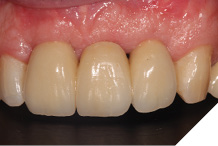

The definitive bridge was fitted and torqued in situ uneventfully after such excellent healing of the provisional bridge (Figs. 31-37).

Fig. 35

Fig. 36

The definitive bridge has integrated well and both hard and soft tissue healing has gone well and very predictably. The chosen biomaterials have integrated well and healed exactly how we would expect them to. The patient was very happy with the aesthetic result especially when we consider what he had been used to preoperatively. The function and phonetics met the patient’s expectations and overall, we were all very happy with the result.